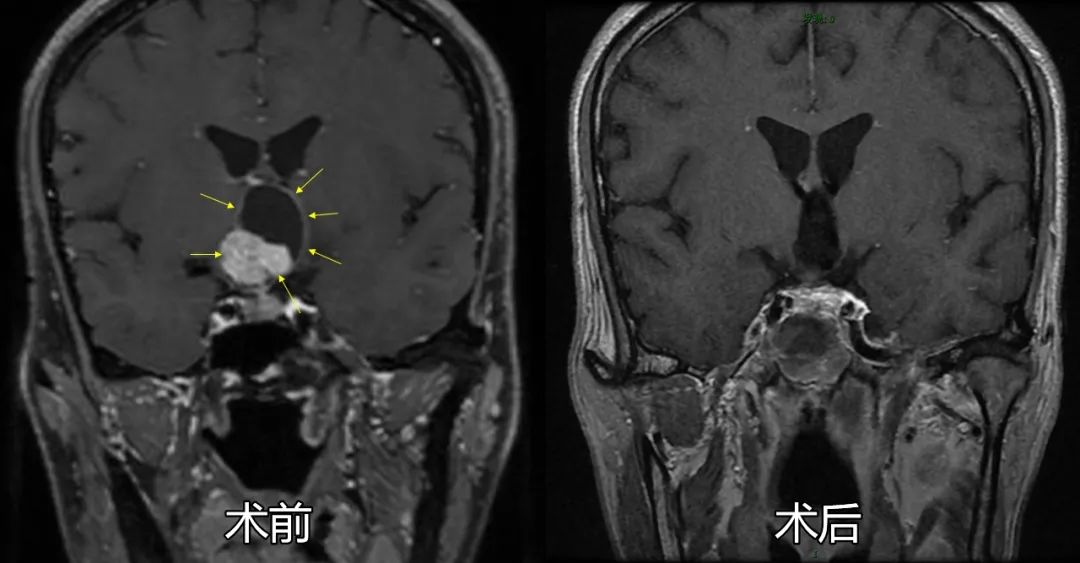

杨先生的颅咽管瘤具体分型为鞍上漏斗结节下丘脑型,肿瘤直径3cm,已生长入第三脑室内,被下丘脑及垂体柄漏斗部包绕,为经鼻内镜手术中治疗难度最高的类型。颅底内镜团队在术前采用三维影像重建等方式,联合内分泌科、影像科、眼科、危重医学科等多学科讨论研究后,为患者量身定制精心设计了内镜手术及综合治疗方案。

手术中,莫伟教授利用神经导航、超声多普勒等多模态辅助手段精准定位,采用神经内镜扩大鞍底手术入路,通过视神经——垂体间隙将这一巨大肿瘤的实质性瘤体及囊壁整体从下丘脑、三脑室壁、垂体柄处仔细剥离,完整切除肿瘤,相应神经血管结构保护完好。

术后当天患者神志已清醒,无神经功能损害表现,复查影像学显示肿瘤已完整切除,周围结构完整,顺利治愈出院,患者及家属对治疗效果十分满意。

术前术后影像学对比显示肿瘤已全切